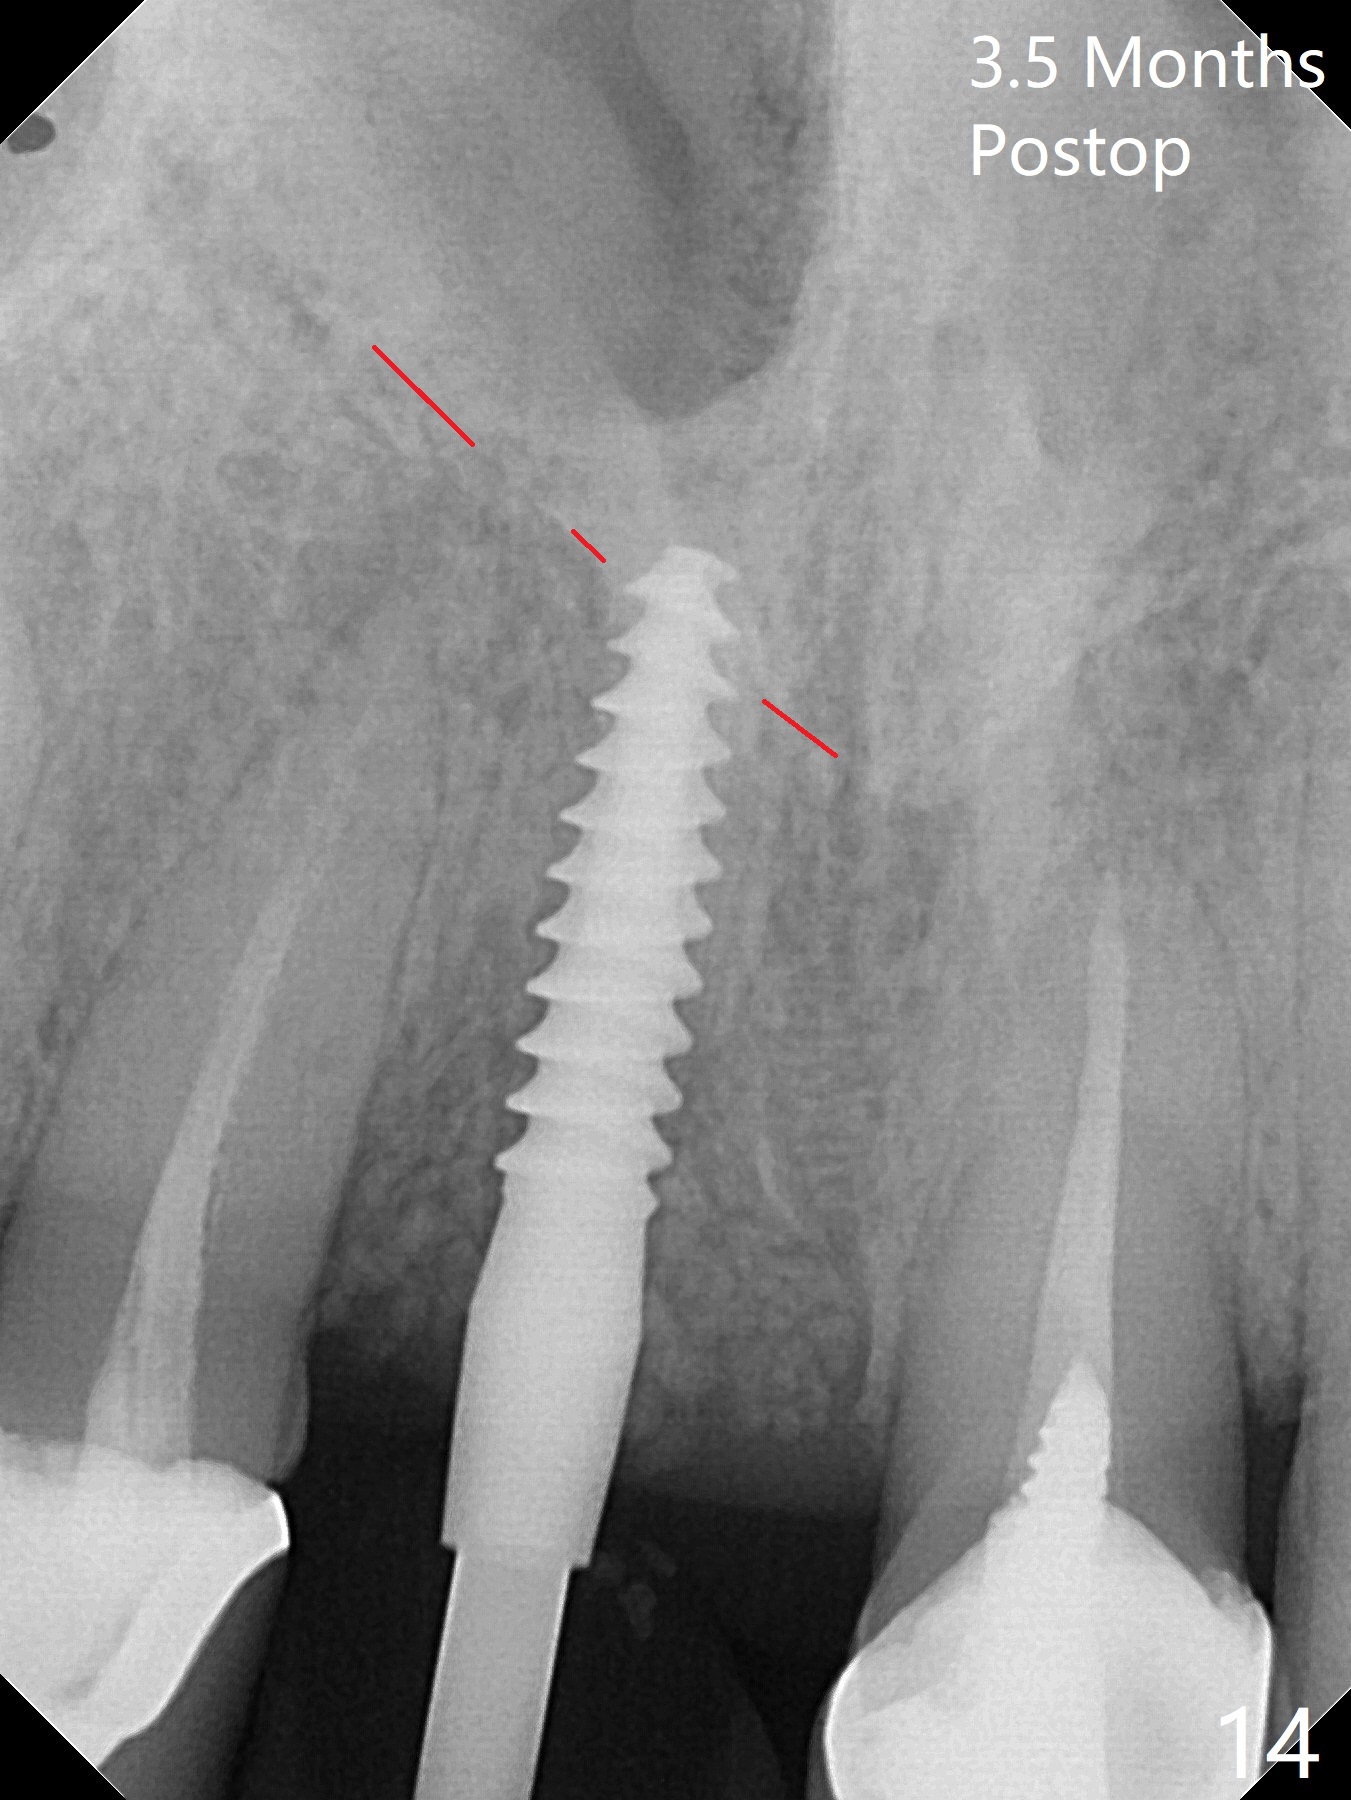

徒手初步钻洞显示方位不对(图一),重新钻洞方位尚可,好像接近鼻底(图二:红线);植入3x11.5毫米一段式植体(图三),3-5个螺纹暴露,植体似乎接近鼻底;旋转植体三趟,植体仿佛卡人鼻底,扭力大约35Ncm,植入粘性骨粉(图四,五:*)前,塞入PRF膜,紧贴颊侧粘膜,促进瘘道愈合。骨粉不仅围绕植体,而且紧贴邻牙牙根(图六(第二轮植骨:overgrafting):<)。病人术后第二周开始使用水牙线,术后三周牙龈健康多了,瘘道消失(图七)。术后六周颊侧骨壁开始塌陷(图八:>),临时牙冠颊侧颈部显得隆起(*)。调整后,牙冠外形改善(图十一至十三),取模前颊侧牙龈缘有可能下降,两个中切牙龈缘可能一致。术后3.5个月骨粉形态(图十四)与术后即刻(图六)有所不同。颊侧牙龈仍红肿轻度触痛(图十五),可能因为临时牙冠不利于局部卫生,所以决定取模制作永久性牙冠。粘固时使用临时胶水,并且涂抗菌素。另外一个可能因素是颊侧骨板薄(图十六:*),细菌感染植体螺纹,永久性牙冠粘固前,拍摄CT(放置cotton roll),必要时,植骨。永久性牙冠远中有缝隙,为了预防病人后悔,使用临时性粘固剂固定(图十七)。Return to No Caries DIO 下一个病例 一段式植体边缘制备 导板与内提升 Xin Wei, DDS, PhD, MS 1st edition 12/22/2020, last revision 06/15/2021